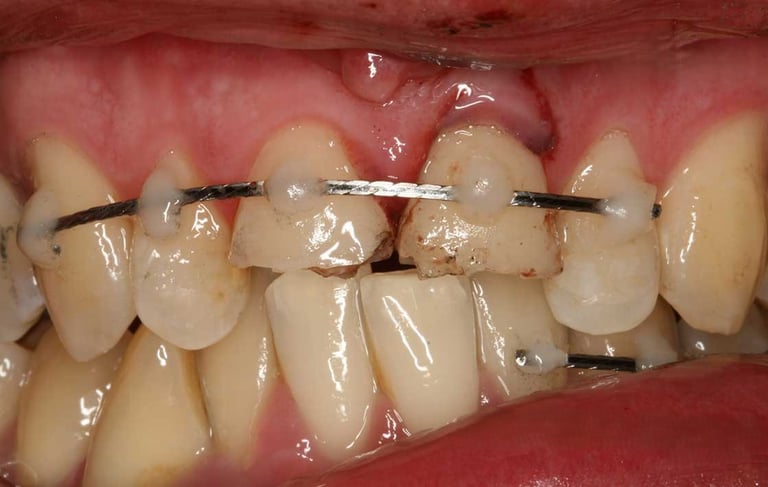

Se maneja el daño causado a los dientes por golpes o accidentes. Puede incluir la reparación de fracturas, el tratamiento de la pulpa y la estabilización del diente afectado.

Tratamiento de traumatismos dentales